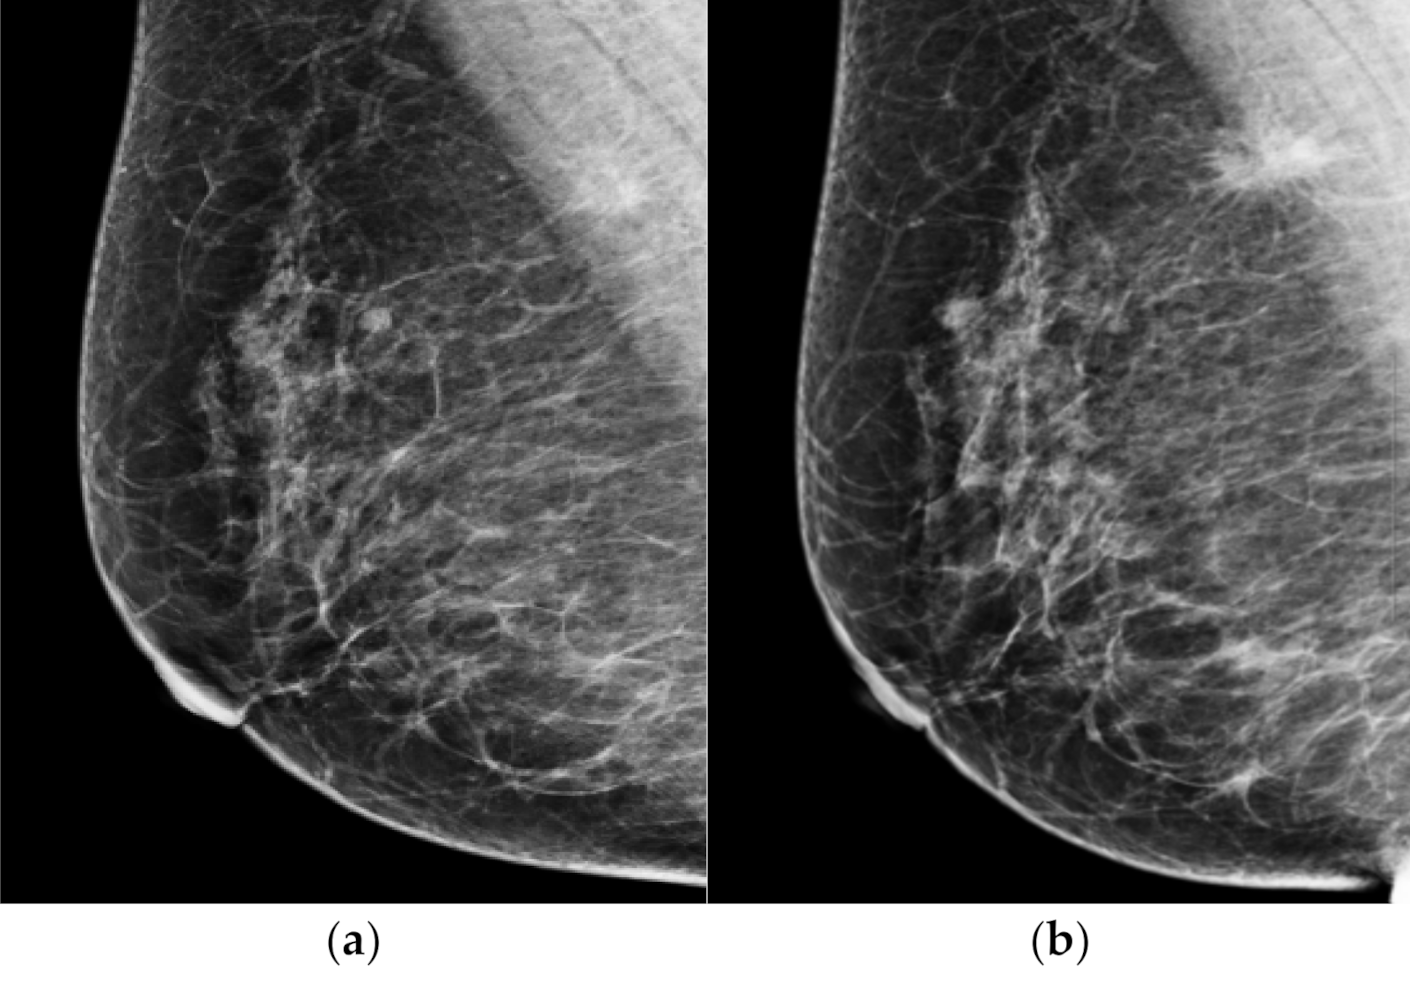

Figure 3.

Representative dismissed case by AI-CAD. A 62-year-old woman classified as negative in a mammography screening (a). When looking at the mammography in retrospect, asymmetry only seen in MLO view was newly developed in the upper and posterior aspect of right breast. This lesion was missed in the prior mammogram. When analyzed retrospectively, AI did not recognize this lesion either. (b) After 18 months of diagnostic mammogram, the previous asymmetry became a spiculated mass and a biopsy confirmed it as invasive cancer.